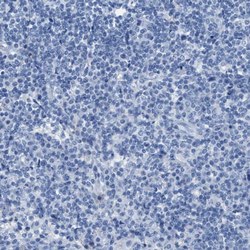

- Immunohistochemical staining of ASGR1 in human lymphoid tissues using ASGR1 Polyclonal Antibody (Product # PA5-52994) shows no positivity in non-germinal center cells as expected.

- Immunohistochemical staining of ASGR1 in human lymph node using ASGR1 Polyclonal Antibody (Product # PA5-52994).